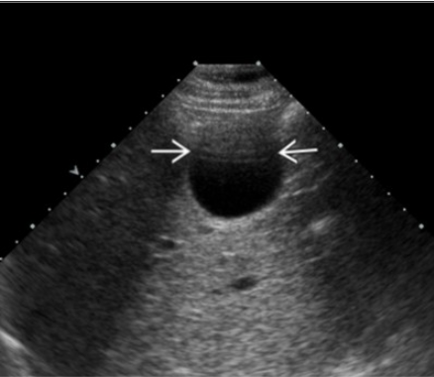

US beam related artifacts:

do side lobe artifacts happen more with linear or curved US arrays?

linear arrays

how do you decrease beam width artifact?